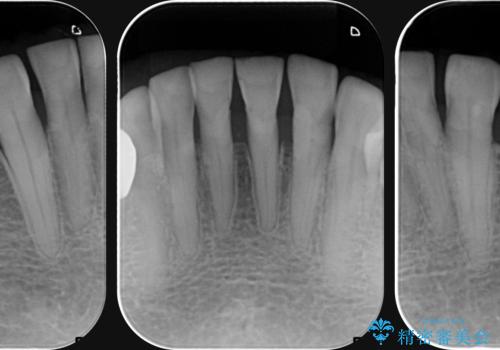

シェーグレン症候群で多発した虫歯 前歯のセラミック治療

- シェーグレン症候群は唾液の分泌が減少し、ドライマウスなど口腔内の乾燥症状が出る疾患です。

唾液分泌が減少すると、虫歯になりやすく、小さな虫歯にコンポジットレジンを充填を繰り返した結果 写真のような継ぎ接ぎだらけの歯になってしまいます。

充填されていたコンポジットレジン・小さな虫歯を丁寧に全て取り除いたのち、歯全体を覆い虫歯の再発予防を期待できるセラミッククラウンで補綴を行います。